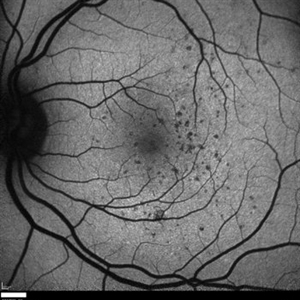

Suspected Multiple Evanescent White Dot Syndrome

Mar 3 2015 by Stuart Alfred, CRA, OCT-C

20 degree view, red free image of left macula of a 28-year-old Caucasian female.

Photographer: Stuart Alfred, CRA, OCT-C, Midwest Eye Institute, Greenwood Indiana

Imaging device: cSLO by Heidelberg engineering (Spectralis)

Condition/keywords: dry age-related macular degeneration (dry AMD), multiple evanescent white dot syndrome (MEWDS), punctate inner choroidopathy (PIC), uveitis